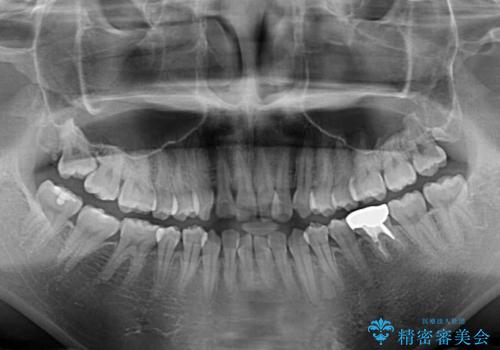

- 前歯のデコボコが気になるとのことで来院された患者様です。

目立たない装置と金属のワイヤーで矯正治療を行うこととしました。

奥の銀歯も気になっていたため、矯正治療後にセラミッククラウンにて補綴することとしました。

1年半程度の期間を見込んでいましたが、上下の真ん中の位置をできる限り合わせるための調整に少し時間がかかってしまいました。